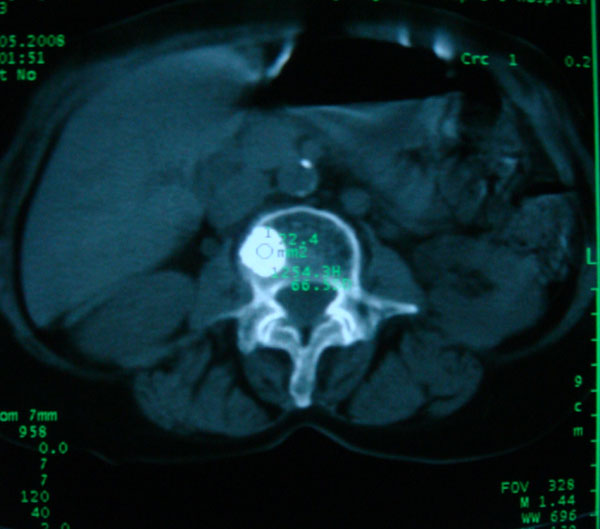

以下是引用卜一在2008-5-24 6:33:00的发言:[br]骨岛!建议定期复查!

以下是引用panyishengct在2008-5-23 23:19:00的发言:[br]骨岛,不排除成骨性转移瘤.

以下是引用pujunzhi在2008-5-24 1:02:00的发言:[br]支持2楼 骨岛,不排除成骨性转移瘤

以下是引用gaoshengjiang在2008-5-24 8:25:00的发言:[br]骨岛,不排除成骨性转移瘤. [br] [br]

以下是引用zjzjr在2008-5-24 14:55:00的发言:[br]骨岛!建议定期复查!